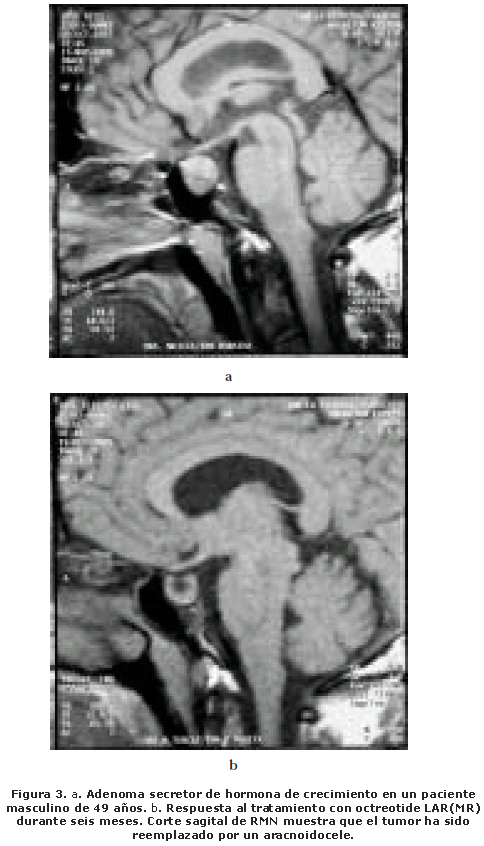

En el Hospital Universitario de Caracas realizamos un estudio clínico en 11 pacientes con acromegalia activa. Luego de probar tolerancia por cuatro semanas con octreótide subcutáneo, los tratamos con Sandostatin LAR(MR) por el lapso de seis meses3. Los síntomas y signos referidos por los pacientes mejoraron y en algunos casos desaparecieron (cefaleas, sudoración, aumento de volumen de partes blandas). Hubo mejoría de la tensión arterial y franca disminución de los niveles de glucemia. Los valores de HC promedio pre tratamiento fueron de 27,3 ng/mL y se obtuvo un descenso hasta 5,03 ng/mL en nueve de ellos al completar la sexta dosis de Sandostatin LAR.

Los niveles de IGF-1 registraron un promedio al inicio del tratamiento de 889 ng/mL con un descenso de los valores hasta 483 ng/mL en nueve pacientes a los seis meses de tratamiento. Las reacciones adversas como flatulencias, náuseas y esteatorrea fueron leves y cedieron sin modificar el tratamiento. En dos casos hubo que interrumpir la terapia porque desarrollaron litiasis biliar sintomática. En dos pacientes la reducción del tamaño del tumor a los seis meses de tratamiento fue sorprendente, solo observándose en la RMN un aracnoidocele secundario (Fig. 3).